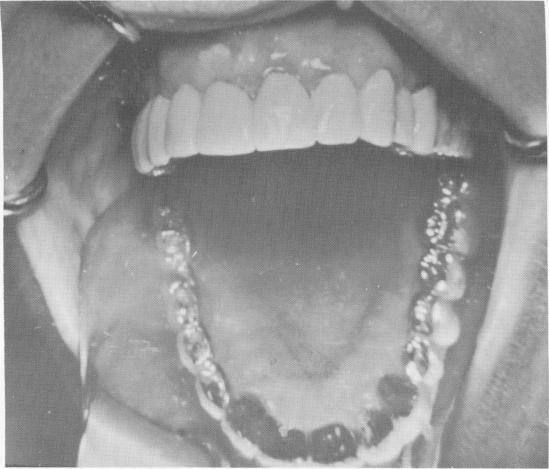

Fig. 4-26. The restoration in place.

2 Final prosthesis placed over Chercheve endosseous spiral-post implant